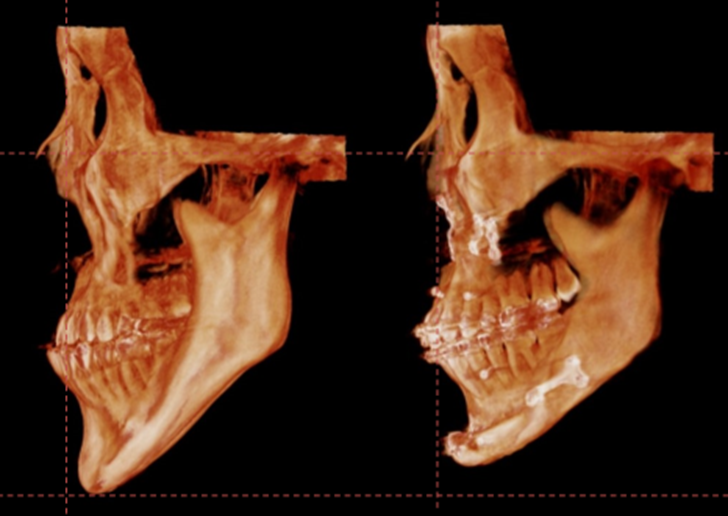

사각턱 부위를 제외한 얼굴 전체의 길이는 줄이고,

치아를 맞추느라 뒤로 들어간 턱끝은 자연스럽게 다시 앞으로 꺼내면서

하악 체부의 볼륨 또한 증가 시키기 위한 윤곽수술이

이 환자분의 수술에서 가장 중요한 과정이었습니다.

턱끝을 2단으로 절골하여 가운데 뼈를 제거하는 샌드위치 테크닉으로

턱끝의 길이를 5mm 줄이면서 앞으로 6mm 전진 시켰고,

단차가 생긴 뒷부분의 하악 하연을 매끄럽게 잘라낸 후 잘 다듬어서

앞턱 전체를 감싸면서 체부볼륨이 증가 될 수 있도록 이식하였습니다.

길이를 줄이기 위해 하악 하연을 잘라내면

어쩔 수 없이 하악체부의 볼륨은 감소하게 됩니다.